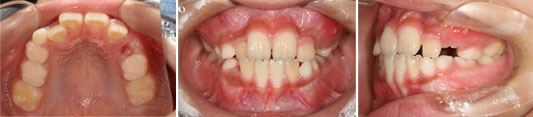

主訴:前歯の歯並びが気になる(叢生)

上下マルチブラケット使用

抜歯部位「14」「24」「34」「45」

概算費用:90万円

初診時(25歳)

2年5か月後

リスク副作用:歯根吸収、あと戻り